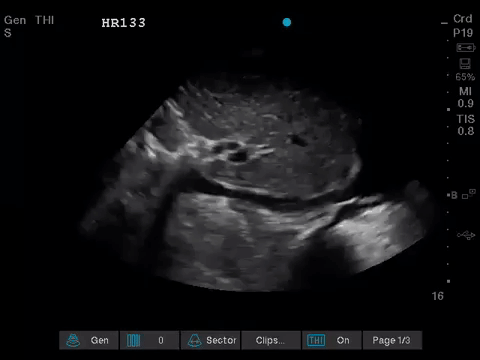

The POCUS consult team was asked to perform an urgent ultrasound for hypoxemia in a 30-year old inpatient.

The patient had been admitted for several weeks under the Hematology service. She had a history of an aggressive hematologic malignancy previously treated with chemotherapy, and appeared to be now having a recurrence of her cancer. Her recent stay had been complicated by multiple infections; including gram-negative bacteremia and persistent Candida fungemia (despite over a week of anti-fungal therapy).

Over the last 36 hours, she was noted to be increasingly tachycardic with soft blood pressures, for which she had received numerous fluid boluses. Her oxygenation had also deteriorated, and she was now requiring an FiO2 of 80% via HFNC to maintain saturations (previously on room air).

Other than her hematologic malignancy and recent complications, she had no significant medical history, and no known cardiopulmonary disease. An echocardiogram from 1 year prior was essentially normal.

The POCUS team was asked to specifically to assess her lungs to help determine the cause of her dramatically increased oxygen requirements.

Before giving their clinical interpretation of the LUS findings, the POCUS team also scanned the heart and vasculature to obtain a more complete picture.